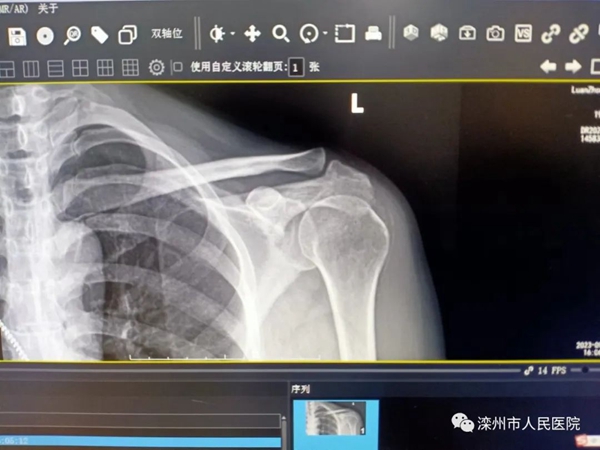

近日,吴女士来到疼痛门诊,被诊断为钙化性肌腱炎,很容易被自己“误诊”,下面就跟大家聊一聊钙化性肌腱炎。

钙化性肌腱炎是由于钙盐在肌腱中沉积而引起的关节炎症的疾病。目前病因不清。常出现在肩部。最容易累及肩部的肌腱如冈上肌、肩胛下肌等。肩钙化性肌腱炎在30岁到50岁人群中比较多见,女性多于男性,在成年人中患病率可达10%。